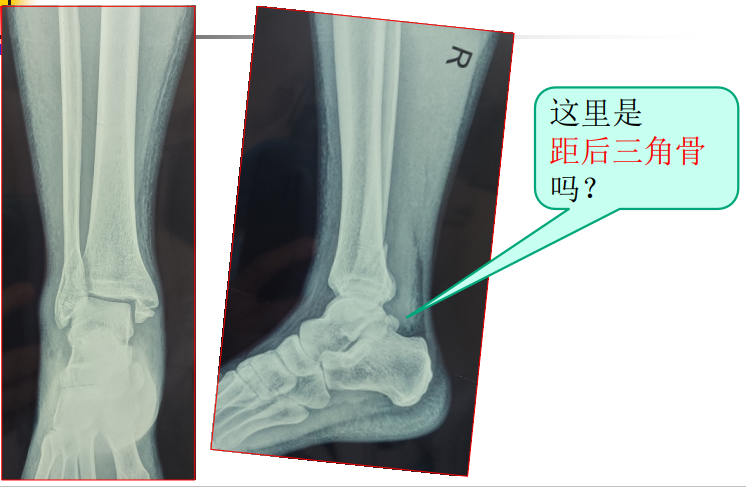

病例一、无症状距后三角骨

病例一、无症状距后三角骨男,49岁,因扭伤踝部来院就诊,X线片提示:踝部骨折。